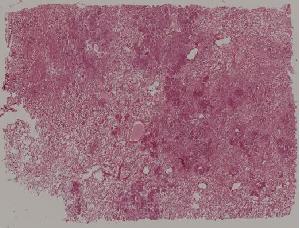

低倍视野

72. Membranous glomerulonephritis

73. Acute glomerulonephritis

74. Crescentic glomerulonephritis

75. Chronic glomerulonephritis